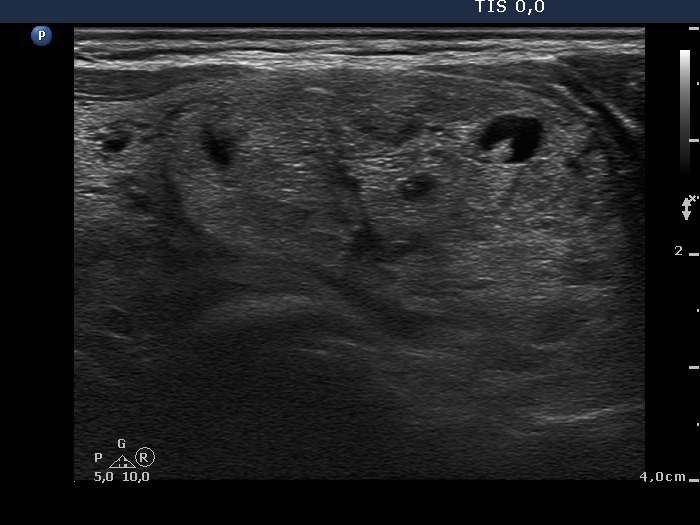

Intranodular hyperechogenic figures - case 608 (ultrasonographic picture 8)

Left side of the isthmus, transverse scan. The small hyperechogenic granules belong to the non-specific subgroup while the more bright echogenic granules and lines dorsal to tiny cystic areas are caused by back wall posterior enhancement.